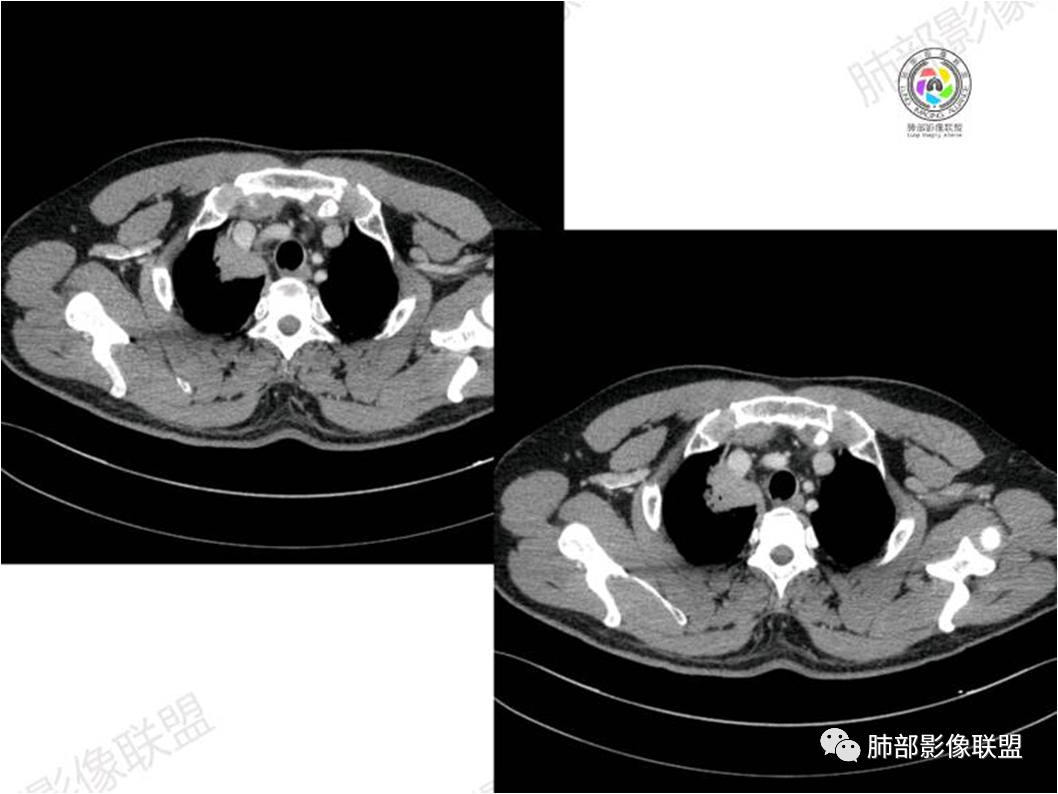

胸部CT:

患者中年男性,咳嗽就诊,无其他不适。胸部CT:右肺上叶尖段上纵膈旁肿块,边界清楚,边缘光滑,内见支气管受压变窄,伴阻塞性改变,增强均匀强化,见血管造影征。综合考虑恶性病变,小细胞肺癌或淋巴瘤。气管镜活检应能明确。

黏膜相关淋巴组织(Mucosa associated lymphoid tissue, MALT)淋巴瘤是来源于黏膜相关淋巴 组织边缘带的低度恶性非霍奇金B细胞淋巴瘤。肺MALT淋巴瘤较为罕见,约占淋巴瘤的0.14%~1%,易被误诊为肺炎或肺癌。

MALT淋巴瘤这一概念最早由Isaacson和 Wright等于1983年提出,其可发生全身具有黏膜的器官或组织,最常见于胃肠道,其次为肺(15%)组织,病因不明,目前多认为与慢性感染、吸烟或自身免疫性疾病有关。肺MALT淋巴瘤是较为罕见的低度恶性肿瘤,多见于50-70岁,男女发病率无明显差异,或男性略多于女性。

⑥肺门及纵隔淋巴结肿大少见;